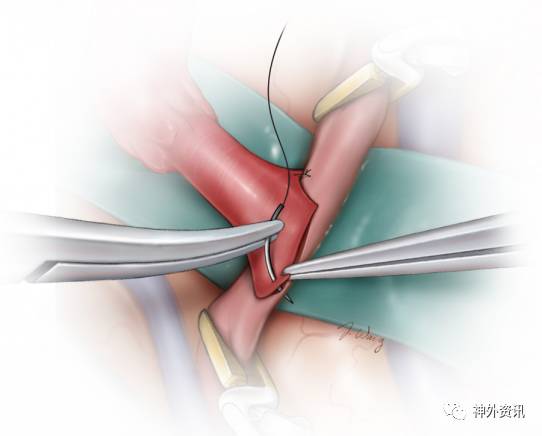

图9. 演示吻合开始时的足跟、趾头对拢。使用9-0或者10-0的不可吸收线,先足跟部后趾头部将STA远端缝合至受血动脉的相应部位。缝针由外向内穿入STA,由内向外穿出受血的MCA分支。

最后,10-0的缝线间断缝合跟、趾两线之间的端-侧吻合口。

吻合口的侧边要么用2根缝线连续缝合,要么间断缝合8-10针。先吻合操作难度大的一侧,所以在闭合对侧之前可以从管腔内检查该侧的吻合情况。若采用连续缝合技术,使线圈保持松弛直至最末一针穿出以及肝素盐水再次冲洗,随后将其理顺依次抽紧并打结。

图10. 应谨记缝针的穿行顺序:在供血动脉为由外向内,受血动脉则相反。如果采用的是间断缝合技术,完成最后一针之前冲洗管腔。注意保持缝针始终与动脉壁垂直以免线孔过大和戳裂管壁。受血动脉上大的破口不可被埋藏于缝线内否则会造成吻合口狭窄。